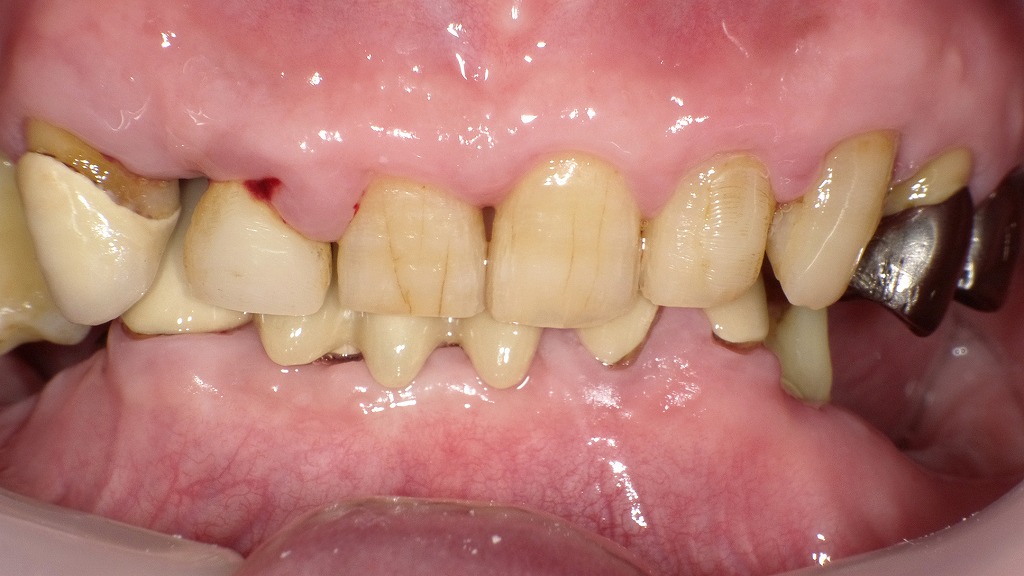

症例3:大人(永久歯)の過蓋咬合

この写真は、**成人の重度の過蓋咬合(かがいこうごう)**を示しています。咬み合わせの深さに加え、歯の摩耗・歯周組織の退縮・欠損歯などが認められ、長期間の不正咬合が全体の口腔機能に影響を及ぼしている状態です。

🦷 過蓋咬合の特徴(この症例の所見)

- 上の前歯が下の前歯を大きく覆い隠している

- 下の前歯が上顎前歯の裏側に深く食い込み、歯ぐきに近接

- 上の前歯に**強い摩耗(すり減り)**が見られる

- 咬合圧の偏りによって、補綴歯(クラウン・ブリッジ)が破損または変色

- 歯周病の影響で歯肉が退縮し、部分的に腫脹・出血がみられ、歯の根が露出している部分がある

- 左右下顎奥歯には抜歯後の欠損部が見られ、咬合支持が失われている